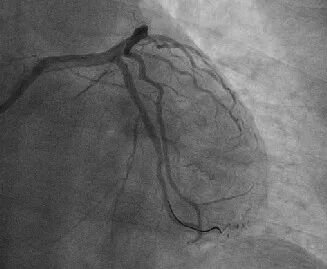

结合造影结果,对回旋支闭塞段精准定位,选取合适冠脉支架置入,成功开通血管并恢复心肌供血(下图↓)。

回旋支慢性闭塞病变是一种常见的心血管疾病,由于血管狭窄或闭塞,导致心肌供血不足,进而引发一系列临床症状。传统的治疗方法往往难以完全解决病变,且存在一定的风险。而逆向造影技术的应用,为治疗这类疾病精准施治保驾护航。经过治疗,患者的症状得到了明显缓解,生活质量得到了显著提高。这一成功案例是我院在心血管领域的一次重要突破。这一技术的成功应用,将为更多患者带来福音,推动医院在心血管领域的发展迈向新的高度。